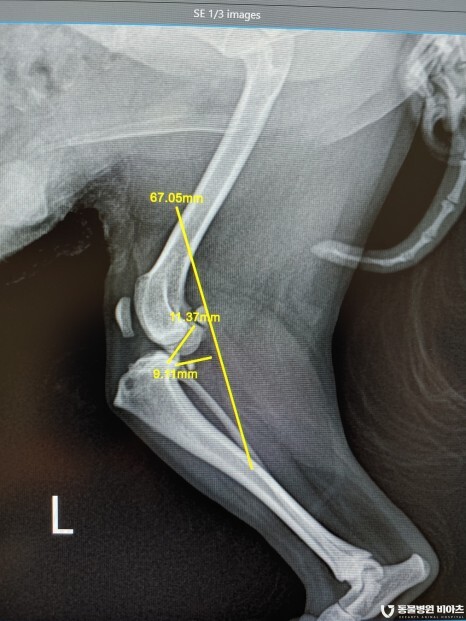

엑스레이 검사 결과

#전십자인대단열

#좌측 후지 슬개골 탈구 3기

#우측 후지 슬개골 탈구 2기

진단이 나왔습니다.